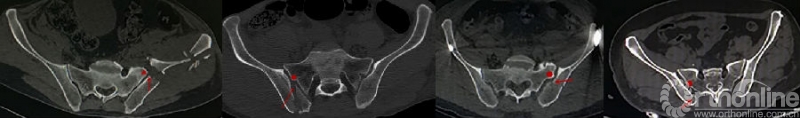

Day等[6]总结了16例新月形骨折的特点,将骶髂关节三等分,根据骶髂关节受累的程度将新月形骨折分为3型,并根据不同分型采用不同的治疗措施。

图3

Day分型把骶髂关节均质化看待,将骶髂关节三等分。Day分型的提出对于新月形骨折的认识和治疗有重要意义,但也有其固有的缺陷,仅采用某个层面的CT二维横断面判断骶髂关节损伤程度,并不能反应实际的关节累及程度[6]。Day分型只将骶髂关节三等分,而没有考虑骶髂间复杂的解剖关系及其在侧方挤压暴力下的相互作用;另外在临床应用中会发现Day分型并不能包含所有新月形骨折类型,Calafi和Routt[4]报道这个比例高达12%。

Day等[6]也发现当骨折线为斜形时,通常在不同层面,骨折线进入骶髂关节的位置是不同的,即当骨折线为斜形时,Day分型在不同层面是变异的。不能被分型系统包含或分型的不确定性给治疗带来困扰,也削弱了分型的实用性和有效性[4、5]。